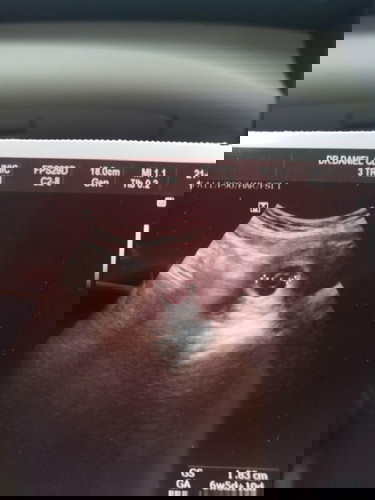

สอบถามหน่อยค่ะ แม่ๆเจอน้องตอนกี่วิคหรอค่ะบ้านนี้หมอบอก 6 วิคยังไม่เจอเลย เหมือนจะท้องลม เรามีเลือดสีน้ำตาลออกมาด้วย แต่ไม่ปวดท้องเลย จะเป็นอะไรหรือป่าวค่ะ

ตอนที่เรา6วีคก็เจอแค่ถุงการตั้งครรภ์เหมือนกันค่ะ แต่เมื่อวันที่20นี้คุณหมดนัดตรวจซาวอีกทีเจอตัวน้องแล้วค่ะ